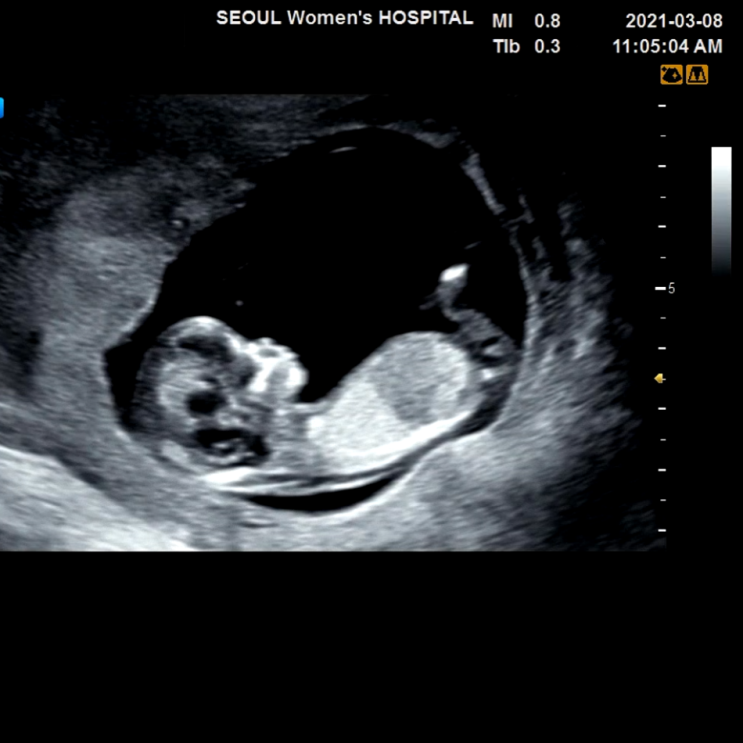

임신일기 : 12w3d 1차기형아검사

12주차 증상 평생없던두통(빈혈수치 아주정상) 아랫배통증(한동안 없다가 생김) 불면증(낮에 그렇게 졸리더...